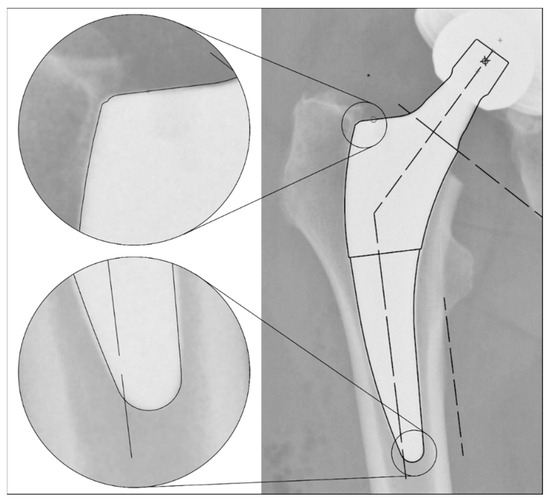

The radiographs were analysed with TraumaCad® software (Brainlab AG, Munich, Germany). We used only standardised deep-centered anteroposterior X-rays of the pelvis, with the central beam perpendicular to the midline and centered over the symphysis, and the legs positioned in 15° of internal rotation with the patient in the supine position. The images were calibrated by measuring the length of the depicted stem from its shoulder to its tip and equating it with the corresponding planning template. In this way, we could avoid any possible errors in our established calibration method with a reference sphere, which can be placed too far away from the central beam or too far away from the film. The measurements of the stem position were subsequently taken on the same axis to neutralise distortions caused by varying flexion and rotation positions of the leg during radiography (Figure 2). The varus/valgus alignment of the stems was determined by measuring the angle between the longitudinal axis of the stem and the longitudinal axis of the femoral canal (Figure 3). Subsidence was determined by measuring the distance from the shoulder of the stem to a clearly definable point at the greater trochanter in the previously determined longitudinal axis of the stem (Figure 4). Due to possible osseous changes over time, such as enthesiopathies or ossifications at the tip of the greater trochanter, defining this point was crucial to measure the correct distance.

Figure 2. Method for calibrating the X-ray images: Equating the maximum length of the stem (from the shoulder to the tip) in the X-ray image to the template size known from the surgical report. This enables a comparable distance measurement even with different X-ray projections due to different rotation and/or varus/valgus position of the leg.